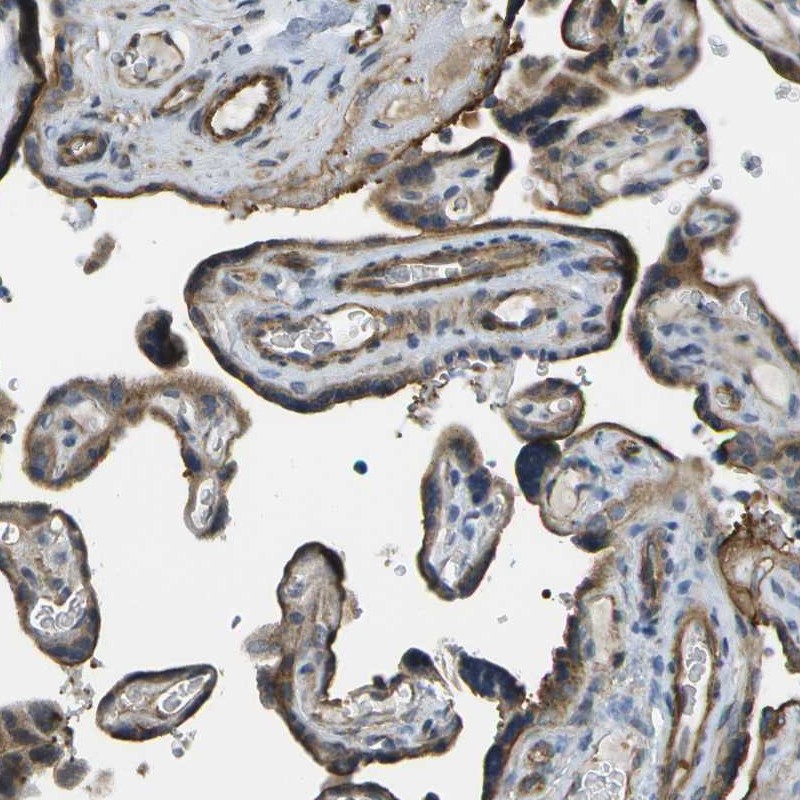

Immunohistochemical staining of human placenta shows cytoplasmic and membranous positivity in trophoblasts and endothelial cells.